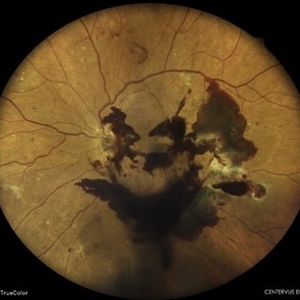

COATS' DISEASE

Mar 14 2022 by Akansha Sharma

MONTAGE OF A 11 YEAR OLD MALE WITH COATS' DISEASE

Photographer: Dr. Akansha Sharma-Retina Foundation, Ahmedabad

Condition/keywords: Coats' disease, exudates, telangiectatic vessels